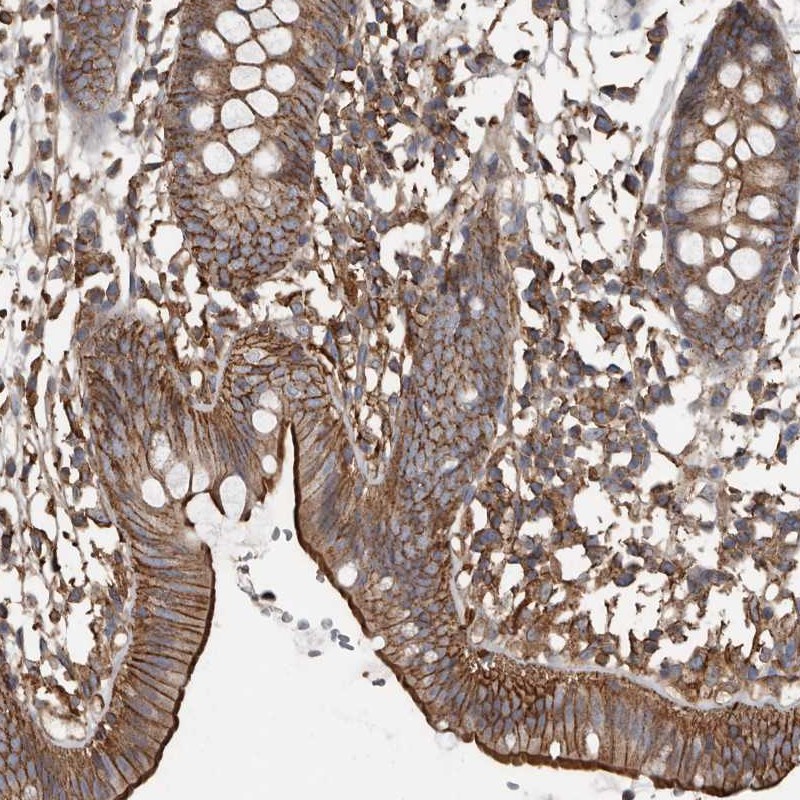

Immunohistochemical staining of human colon shows distinct membranous positivity in glandular cells.